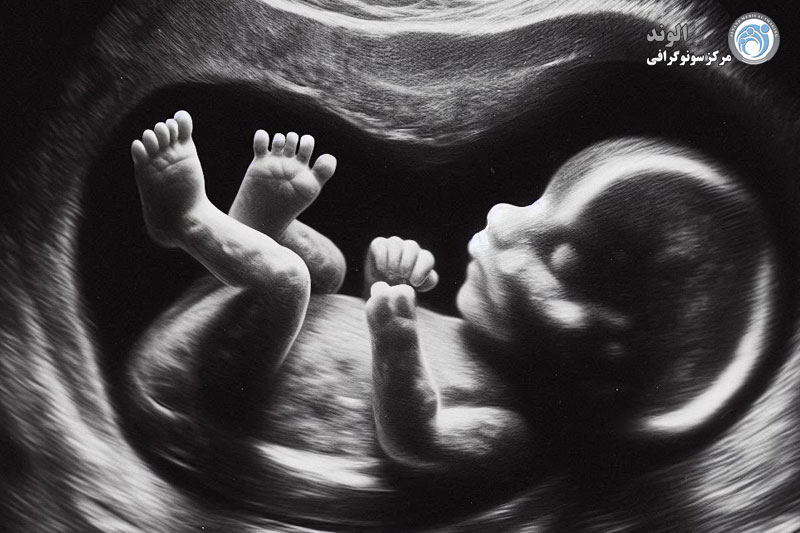

تصویربرداری از جنین

از آنجایی که اولتراسوند از امواج صوتی برای ایجاد تصاویر خود استفاده می کند، نشان داده شده است که هم برای مادر و هم برای کودک بی خطر است. معاینه کامل جنین با استفاده از سونوگرافی شامل تصویربرداری از سر، قلب، کلیه ها، ستون فقرات، معده، بند ناف، مثانه و جفت نوزاد برای تعیین وجود هر گونه ناهنجاری است. از همین معاینه جنین نیز می توان برای بررسی احتمال چند قلو، جهت گیری غیرعادی و در صورت قرارگیری صحیح جنین، جنسیت را نیز تعیین کرد. با اندازه گیری جنین، پزشک می تواند سن حاملگی نوزاد را نیز تعیین کند تا به تاریخ بارداری کمک کند.

در دوران بارداری، تکنیک های اولیه سونوگرافی جنین را می توان در زمان های مختلف برای ارزیابی رشد جنین در شکم انجام داد. امروزه همزمان با پیشرفت علم و فناوری، تکنیک سونوگرافی ناهنجاری جنین بسیار رایج شده است، مادران بسته به انتخاب خود می توانند سونوگرافی دو بعدی، سونوگرافی سه بعدی یا سونوگرافی چهار بعدی را انتخاب کنند.

سونوگرافی جنین اساسا یک ابزار تصویربرداری است که به ثبت ناهنجاری ها در تصاویر جنین کمک می کند، بنابراین سونوگرافی اولیه جنین فقط به بررسی ناهنجاری های مورفولوژیکی کمک می کند. به عنوان مثال، آسیب شناسی اختلالات متابولیک، ناشنوایی مادرزادی یا ناهنجاری های خونی